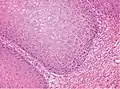

Low-magnification micrograph of penile verrucous carcinoma. The tumor is characterized by prominent papillomatosis.[10]

High magnification. There is prominent acanthosis. The tumor front is broad-based and pushes the subepithelial tissues.[10]